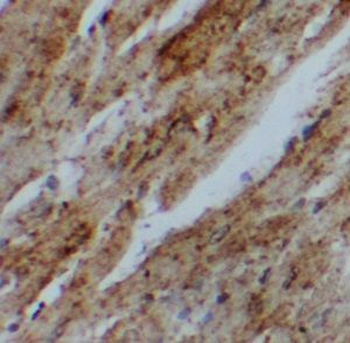

UBAC1 Antibody immunohistochemistry analysis in formalin fixed and paraffin embedded human prostate carcinoma followed by peroxidase conjugation of the secondary antibody and DAB staining.